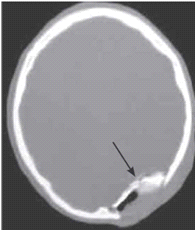

קובץ:גולגולת316.png

גולגולת316.png (196 × 231 פיקסלים, גודל הקובץ: 16 קילו־בייטים, סוג MIME: image/png)